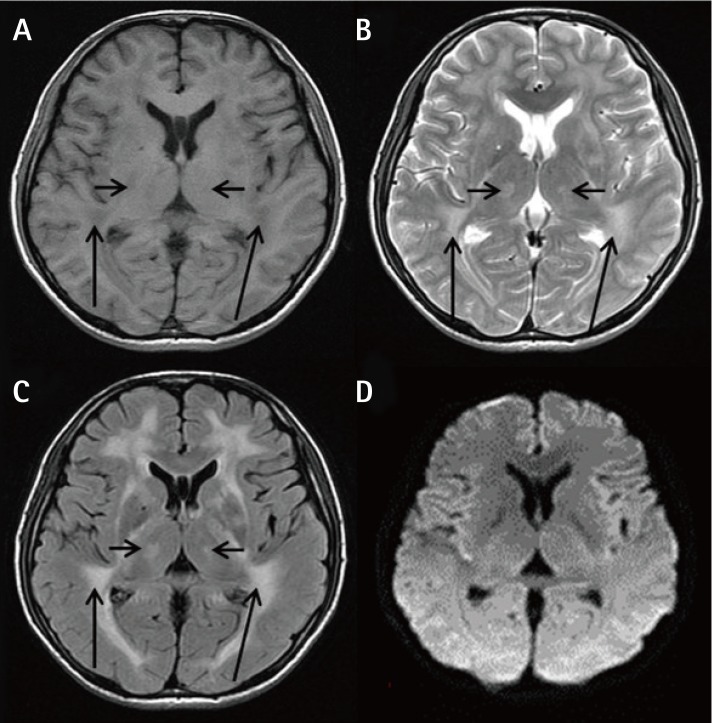

The laboratory test results demonstrated a triglyceride (TG) level of 18.8 mmol/L. His abdominal and pelvic computed tomography scan revealed a small angle between the superior mesenteric artery and abdominal aorta (Figure 1), low stomach tension (Figures 1A and 1B), a partial horizontal segment of the duodenum under pressure (Figures 1A and 1C), and significantly expansive intestines with thickened walls (Figure 1C), as well as a severe fatty liver (Figure 1D). An MRI scan of the brain presented white matter changes (Figure 2). A genetic test revealed a homozygous TYMP gene (c.217G > A) mutation in the nuclear DNA. Accordingly, MNGIE was diagnosed. Our patient was treated with capacity expansion, water-and-electrolyte balance maintenance, gastrointestinal decompression, total PN (TPN) therapy, containing energy at 33.69 kcal/kg/day, and fat emulsion suspension. Seven days later, TG was administered at 4.88 mmol/L, as well as a Calvin injection with supplements of energy at 40 kcal/kg/day, soybean fat emulsion at 1.94 g/kg, and l-carnitine at 1 g. Ten days later, the patient was administered TG at 15.17 mmol/L. Thereafter, an individualized formulation was administered, containing energy at 46 kcal/kg/day, structured triacylglycerol emulsion at 1.43 g/kg, and l-carnitine at 3 g. After 4 days, the TG dose was reduced to 11.09 mmol/L. Two weeks after admission, both EN and PN were provided, together with supplements of vitamins B1, B6, and B12; vitamin C; folic acid; Q10; and probiotics. The details of the examination and nutrition therapy are shown in Table 1. One month later, the patient was discharged on his own and was provided with Weaver (Nestlé) at 600 kcal/day only. He died 5 days after discharge.

Figure 1

Abdominal and pelvic computed tomography scans. (A): The angle between the abdominal aorta and superior mesenteric artery (short white arrow) was significantly smaller. (A) and (B): The position of the stomach was significantly lower. The stomach and intestines were significantly dilated with large quantities of liquid. (C): The gastrointestinal wall was uniformly thick with homogeneous enhancement (long white arrows). (D): The density of the whole liver was significantly reduced, and the volume was elevated.

Figure 1 Abdominal and pelvic computed tomography scans. (A): The angle between the abdominal aorta and superior mesenteric artery (short white arrow) was significantly smaller. (A) and (B): The position of the stomach was significantly lower. The stomach and intestines were significantly dilated with large quantities of liquid. (C): The gastrointestinal wall was uniformly thick with homogeneous enhancement (long white arrows). (D): The density of the whole liver was significantly reduced, and the volume was elevated.